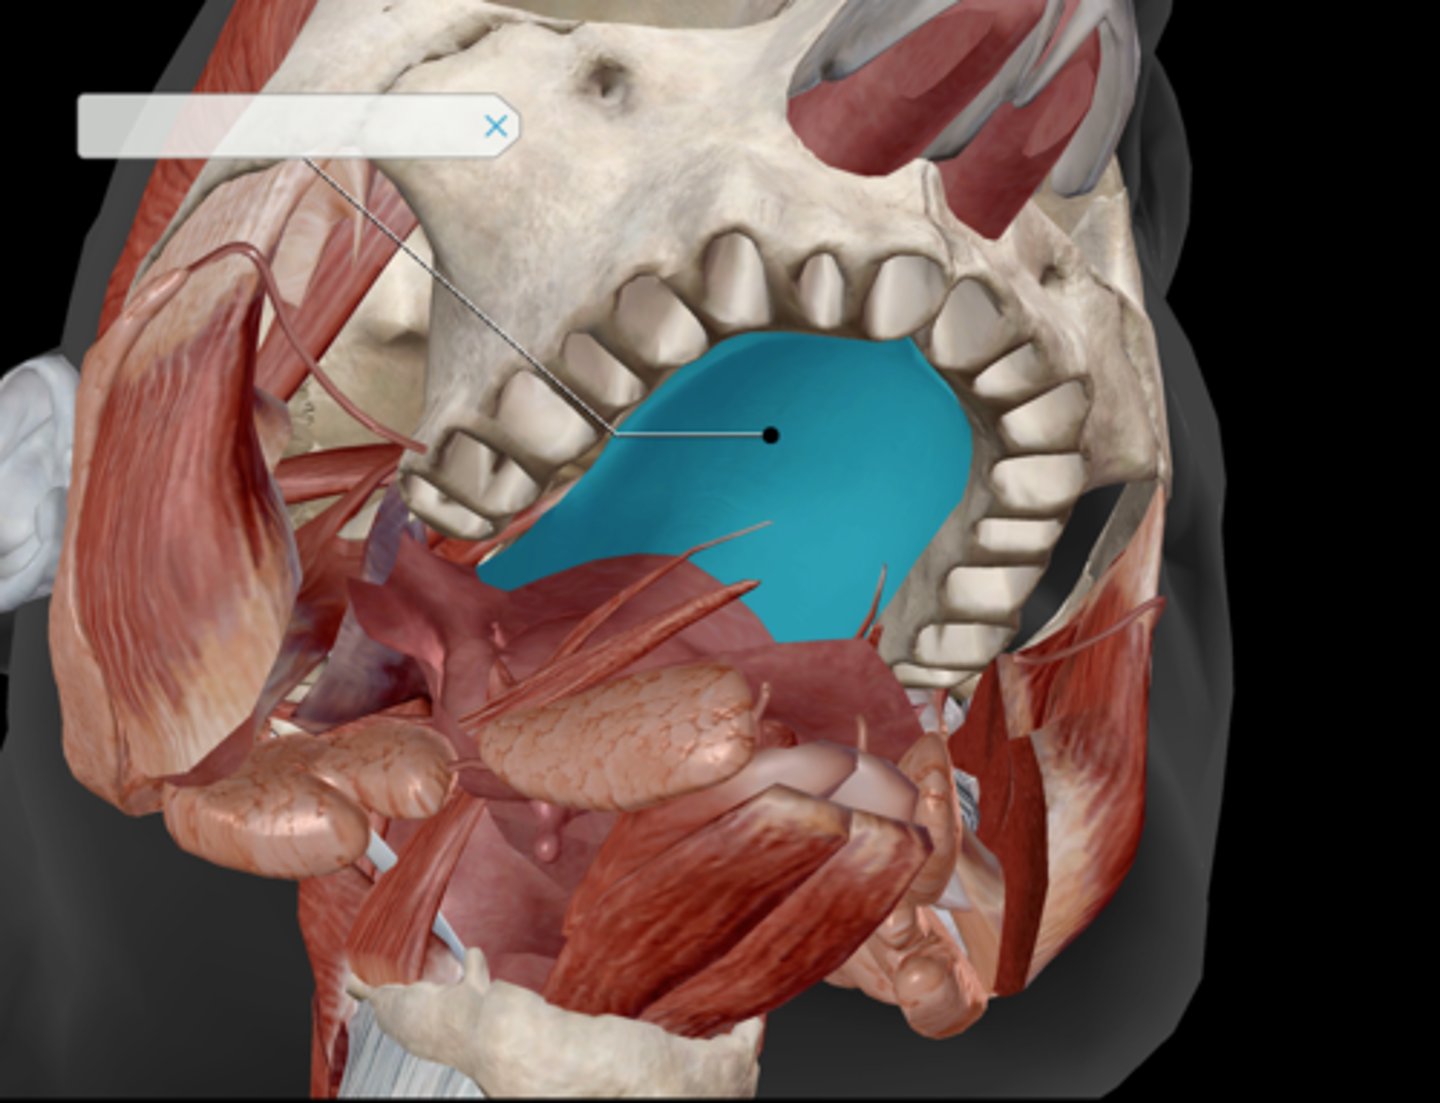

Tongue

Hard palate

Soft palate

Palatine tonsil

Uvula

Incisor

Canine (cuspid)

Premolar (bicuspid)

Molars

Tooth structure

Parotid gland

Submandibular duct

Sublingual gland

Superficial masseter

Deep masseter

Temporalis